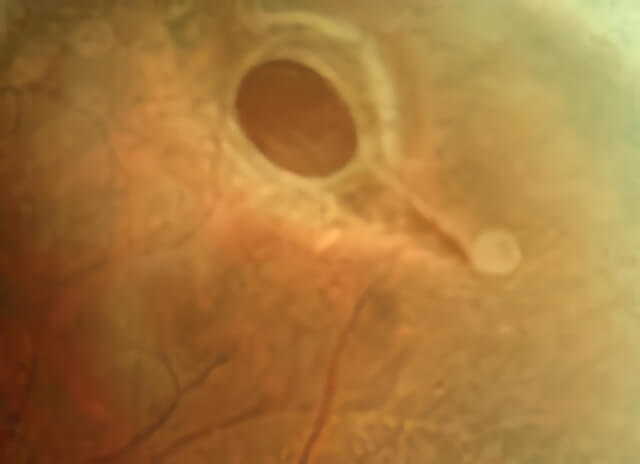

If there are horseshoe-shaped retinal tears associated with lattice degeneration, they are treated thermally with either laser or cryotherapy. Lattice with and without atrophic holes is often not treated, unless the lattice is associated with early sub-retinal fluid, or is found in the other eye in a patient who has suffered a previous retinal detachment. Sometimes, lattice is treated pre-operatively for other types of eye surgery.

A large hole is present within this area of lattice degeneration.